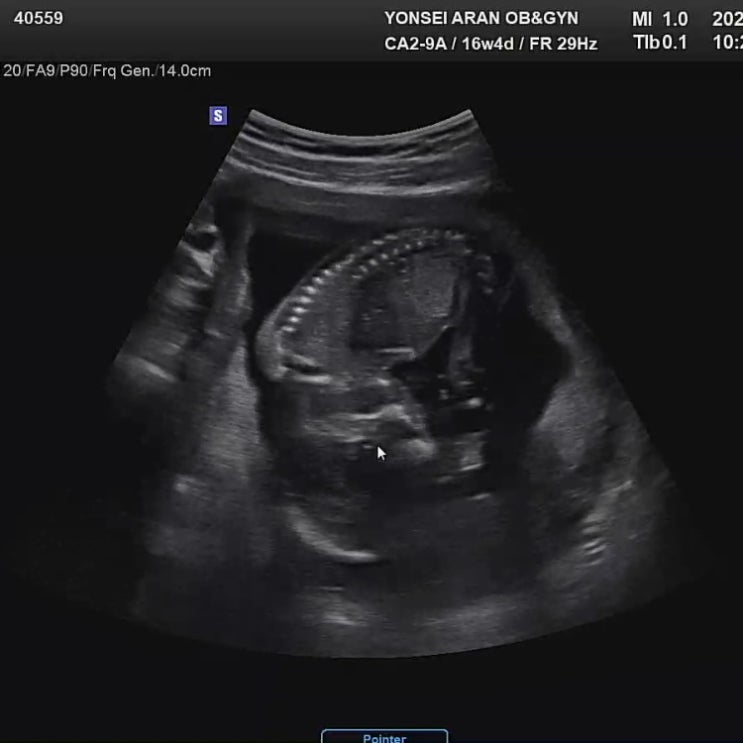

[임신 16주차] 2차 기형아 검사 우리아기 성별은?! ??

임신 16주차 증상 ? 입덧에서 해방된다. 속이 더부룩 해지면서 소화가 안된다. 허리가 뻐근하다. 배가 ...